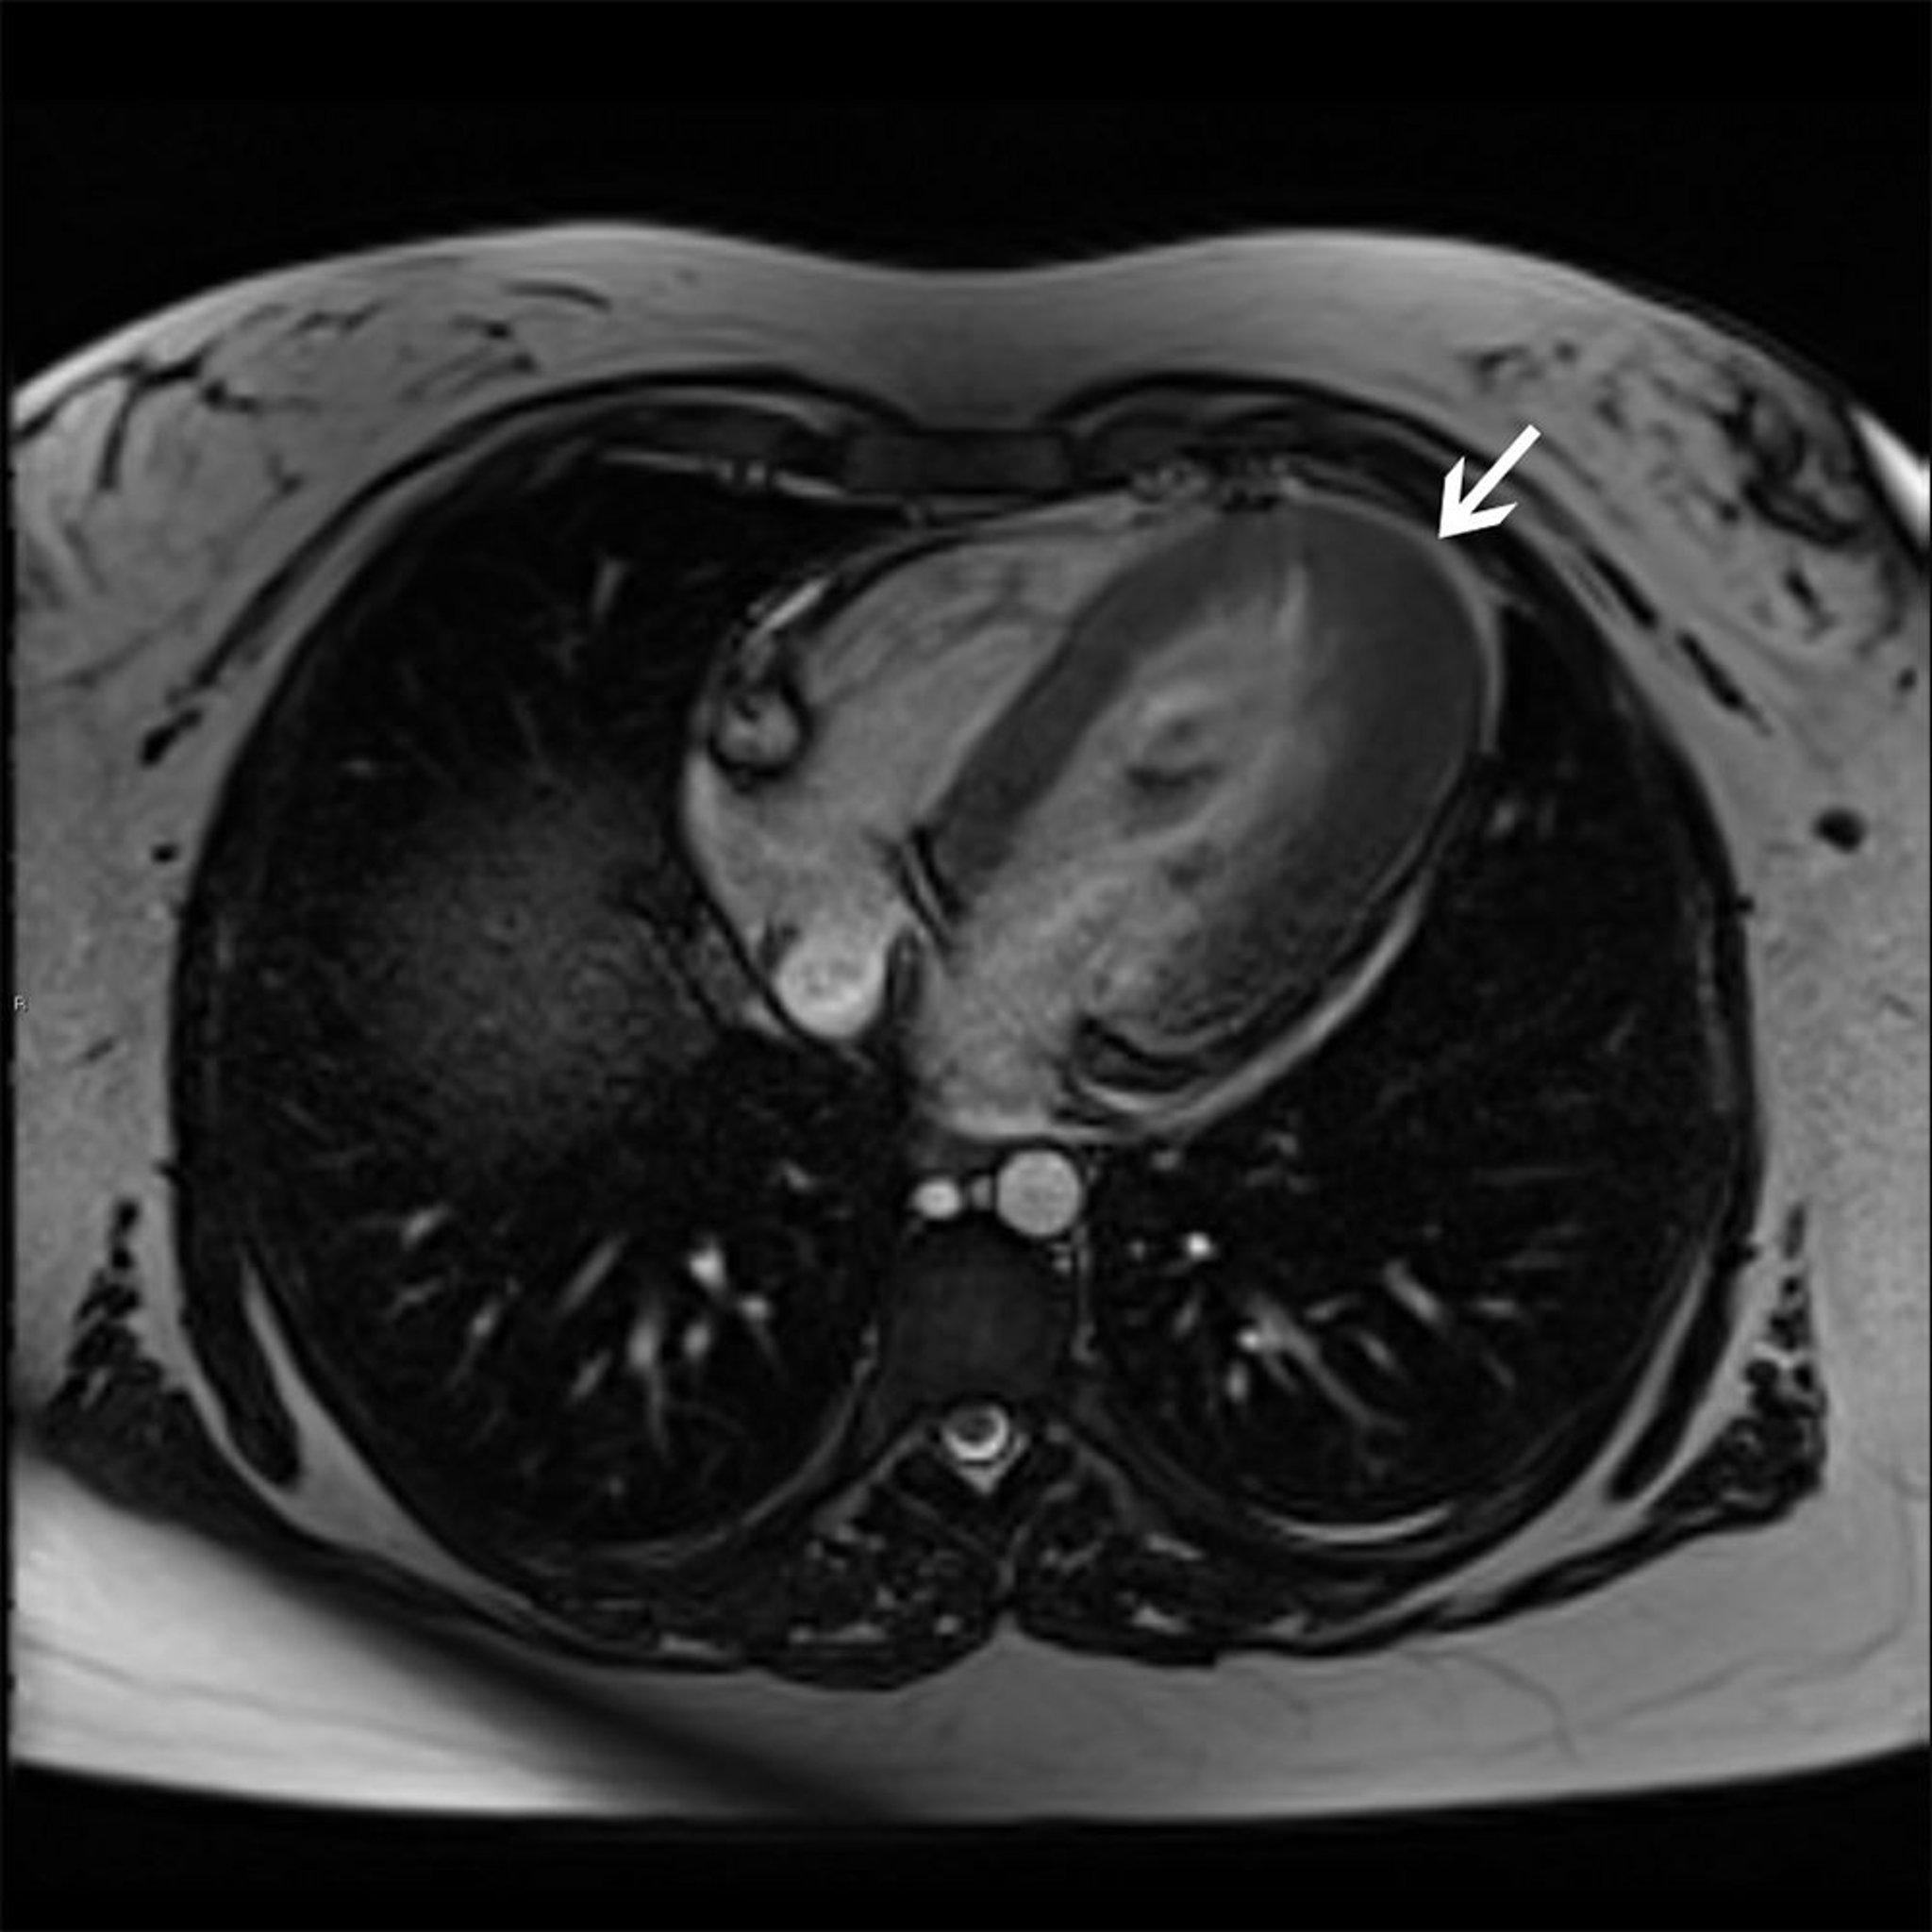

MRI tim này cho thấy thể phì đại mỏm (mũi tên) của bệnh cơ tim phì đại.

© 2017 Bác sĩ Elliot K. Fishman.